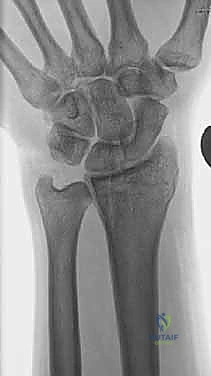

1. الأشعة السينية (X-rays): بوضعيات متعددة (أمامية خلفية، وجانبية دقيقة). الوضعية الجانبية الحقيقية (True Lateral) حاسمة لاكتشاف أي خلع جزئي في المفصل (DRUJ).

2. الأشعة المقطعية ثلاثية الأبعاد (3D CT Scan): تُستخدم في الكسور المفتتة أو كسور رأس الزند المفصلية المعقدة، حيث تعطي خريطة دقيقة للجراح قبل الدخول لغرفة العمليات.

3. الرنين المغناطيسي (MRI): يُطلب عند الاشتباه القوي بوجود تمزقات في الأربطة والمركب الغضروفي (TFCC) التي لا تظهر في الأشعة السينية.